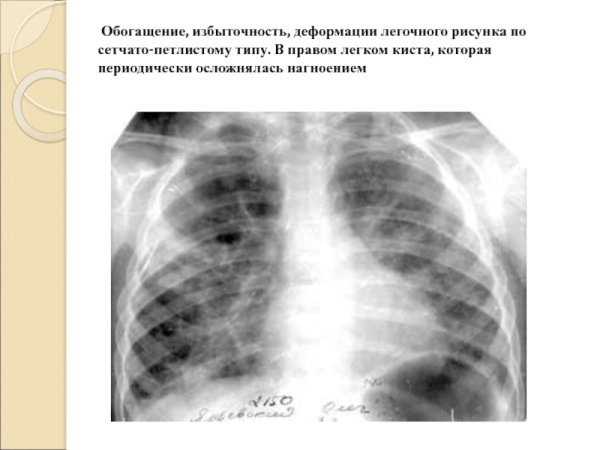

Деформация легочного рисунка - это состояние, при котором образование и распределение сосудистых и бронхиальных структур в легких претерпевает изменения. Это может быть следствием различных заболеваний, например, хронической обструктивной болезни легких (ХОБЛ), бронхоэктазов, фиброза легких или эмфиземы. Как результат, легочный рисунок становится нарушенным, что приводит к ограничению функции дыхания и возможному ухудшению общего состояния пациента. Для диагностики и оценки деформации легочного рисунка используются различные методы, такие как рентгенография грудной клетки, компьютерная томография или магнитно-резонансная томография. Лечение деформации легочного рисунка зависит от основного заболевания и может включать фармакотерапию, физиотерапию или хирургическое вмешательство.